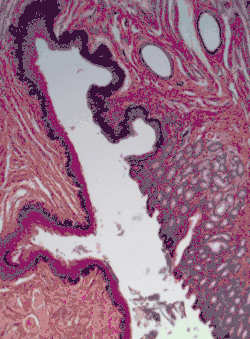

Section of the human skin showing the stratified squamous epithelial surface, referred to as the epidermis. The layer of keratin here is named the stratum corneum.

In the epidermis of skin in mammals, reptiles, and birds, the layer of keratin in the outer layer of the stratified squamous epithelial surface is named the stratum corneum. Stratum corneum is made up of squamous cells which are keratinized and dead. These are shed periodically.

Keratinized

Keratinized surfaces are protected from absorption by keratin protein. Keratinized epithelium has keratin deposited on the surface which makes it impermeable and dry. Examples of keratinized stratified squamous epithelium include skin, the epidermis of the palm of the hand, and the sole of the foot,[5] and the masticatory mucosa.